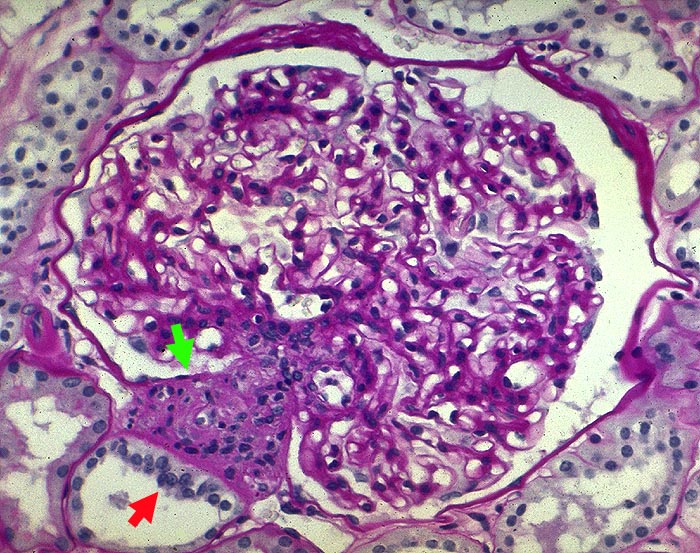

Morphologisch handelt es sich bei der membrano-proliferativen Glomerulonephritis um eine durch Mesangium- und Kapillarwandschädigungen charakterisierte Immunkomplexglomerulonephritis (Synonym: mesangiokapilläre Glomerulonephritis). Man unterscheidet einen Typ I mit subendothelialen Depots (> 2696) von einem Typ II mit dichten intramembranösen Ablagerungen (besser als intramembranöse Glomerulonephritis oder dense deposit disease bezeichnet) (> 2264).

Die Erkrankung läuft phasenhaft ab (> 2630): initial subendotheliale Depots begleitet von neutrophilen Granulozyten und Monozyten in den Schlingenlumina (> 2636), später mesangiale Zellvermehrung, Auswandern in die Schlingenperipherie (mesangiale Interposition) und subendotheliale Basalmembranneubildung (Tramgleisbild aufgrund einer Basalmembranverdopplung). Schliesslich Abnahme der subendothelialen Depots und zunehmende mesangiale Matrixvermehrung zum Teil mit knotiger Umwandlung der Mesangiumfelder.

• Verbreitertes hyperzelluläres Mesangium (mehr als drei Zellen pro Mesangiumareal mit überlappenden Kernen).

• Die glomerulären Basalmembranen wirken schon in der Übersicht deutlich verdickt und erscheinen verdoppelt.

• Monozyten und neutrophile Granulozyten in den Kapillarschlingen.